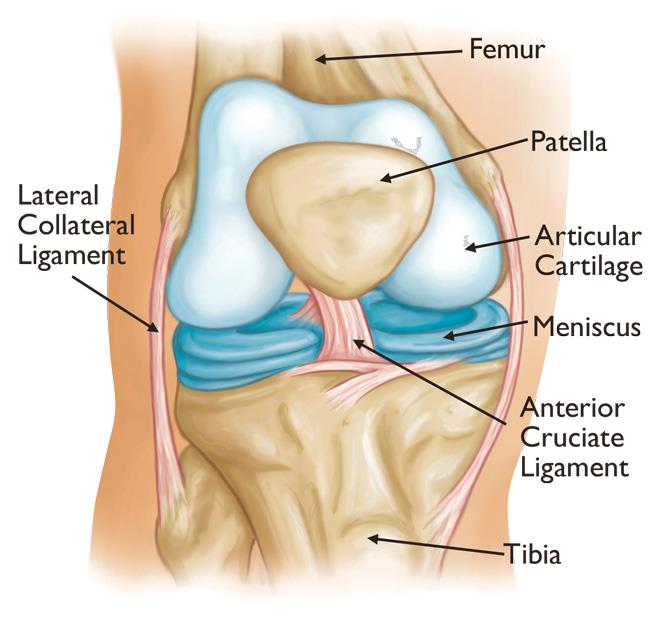

جراحی تعویض زانو یا آرتروپلاستی کامل مفصل زانو یا توتالنی ( Total Knee Arthroplasty (TKA)) نوعی عمل جراحی برای بازگرداندن عملکرد زانوی آسیب دیده و کاهش درد است .در این عمل جراحی ، قطعات فلزی و پلاستیکی مخصوصی جایگزین مفصل آسیب دیده زانو می شود. این روش جراحی معمولا برای افرادی که دچار آتریت شده اند و قادر به انجام فعالیت های روزانه خود به دلیل آسیب زانو ، نیستند انجام می شود. آناتومی مفصل زانوی سالم آناتومی مفصل زانوی سالم